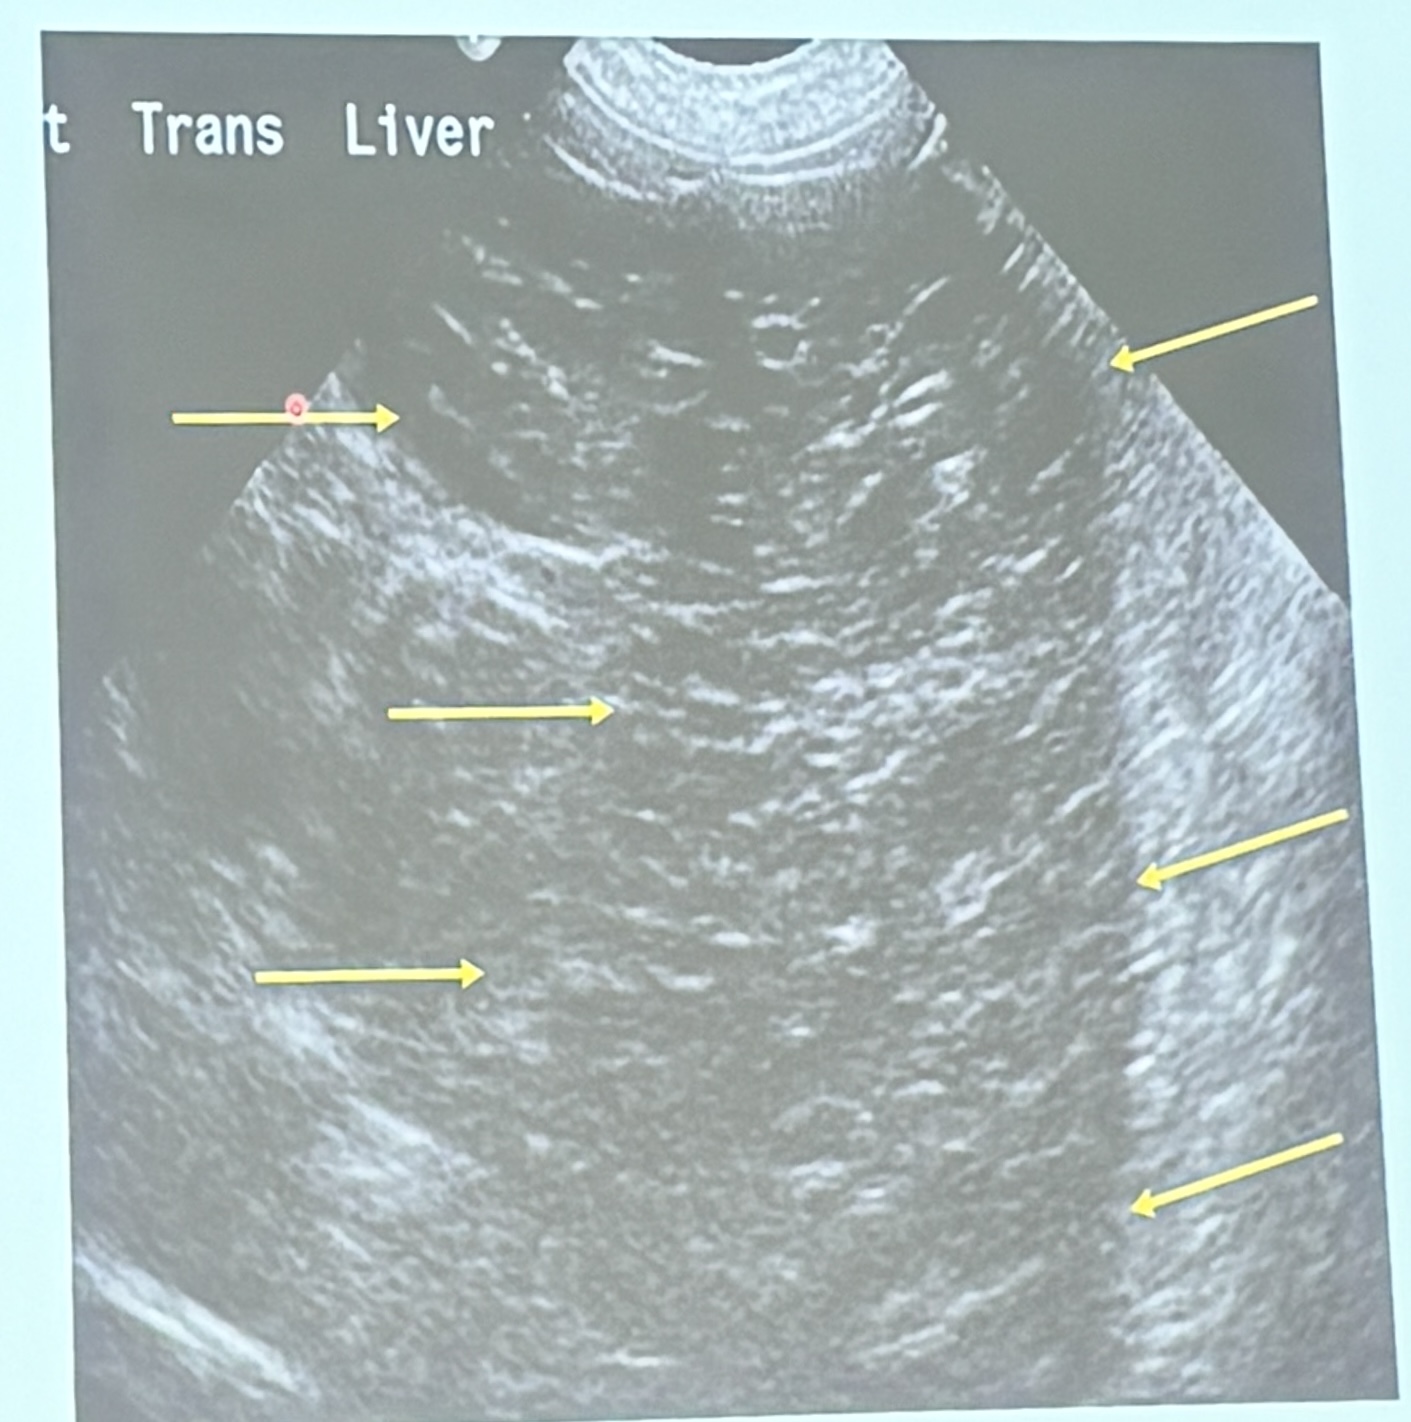

This is a longitudinal scan of the liver from an 8yo MN MBD diagnosed with lymphoma. What are the ultrasonographic findings?

Diffuse hypoechogenicity